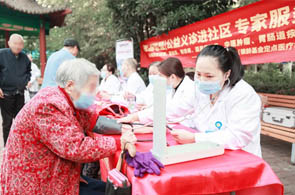

了解更多 +原北京301医院潘秀臣教授面对面,共解痛风风湿骨病难题